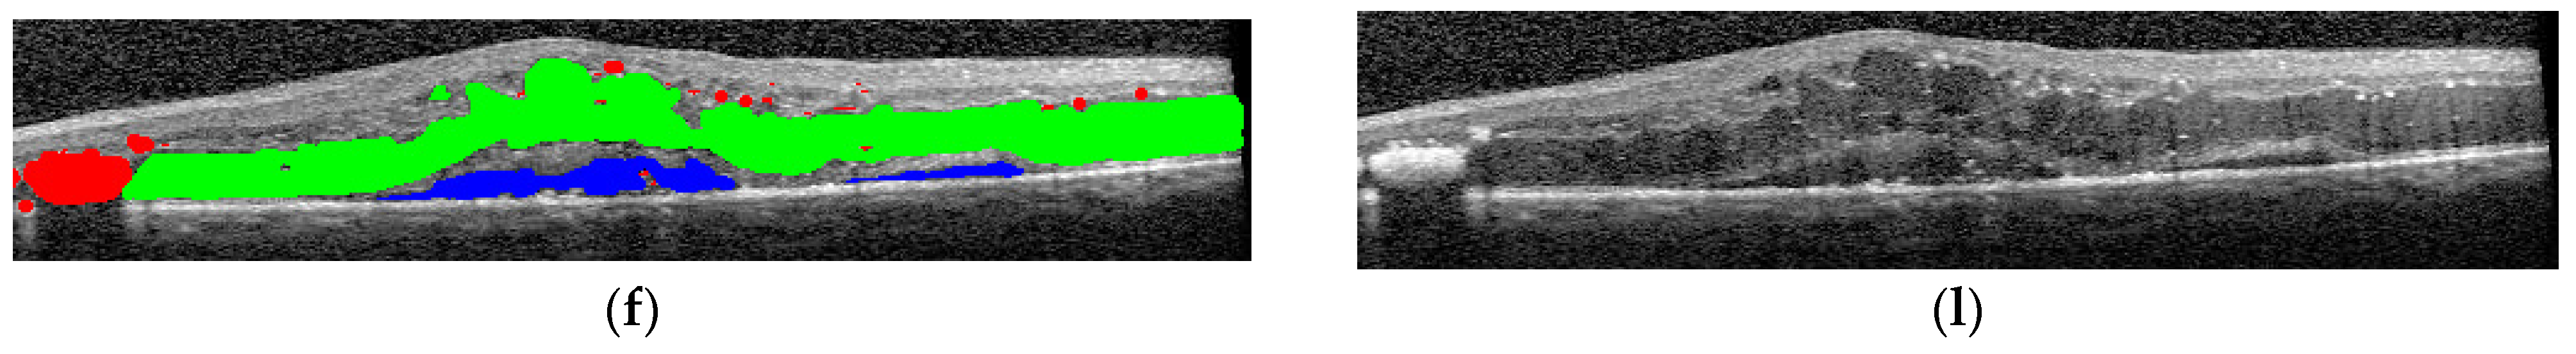

The final step was to use the selected architectures to identify the presence of different disease biomarkers (intraretinal cystoid spaces, HF, subfoveal ND, and neovascular AMD) in the images. In order to do this, all the images were annotated in terms of presence of the mentioned biomarkers. Apart from this, a smaller number of OCT images were manually annotated at the pixel level. All the annotations were performed at the OCT B-scan level, and not at the patient level (Figure 4). Nonetheless, the information about a patient being healthy or not is available.

Figure 4.

(a–f) Examples of pixel-level image annotations for training. The left column contains human annotated macular images, while the right column contains original OCT images. (a,g) edema and cystoid spaces; (b,h) edema and cystoid spaces; (c,i) cystoid spaces and hyperreflective foci (HF); (d,j) neurosensory detachment (ND) and HF; (e,k) cystoid spaces; (f,l) combined lesions. Green—edema and cystoid spaces; blue—ND; red—HF.